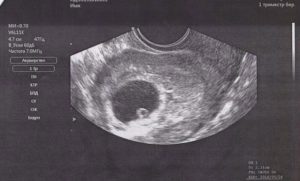

5 недель. Хорошо виден плодный мешок, а также отек эндометрия

На этом сроке УЗИ используется для того, чтобы подтвердить саму беременность. Через пару недель плодное яйцо становится больше и гораздо заметнее.

На каком же сроке видно сам эмбрион на экране аппарата УЗИ? Разглядеть его можно только с пятой недели беременности: видно будет продолговатый объект, крепящийся будущей пуповиной к стенке плодного яйца.